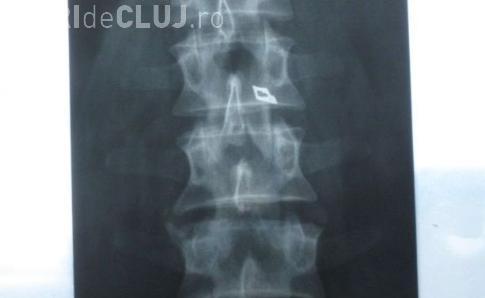

Oradeanul a fost operat in 2004 la Clinica de Neurochirurgie din Cluj, de o echipa de medici condusa de chirurgul Stefan Florian. Barbatul a fost externat si dupa circa un an a inceput sa se simta rau. "Am inceput sa ma simt rau si aveam o umflatura si o roseata la spate in zona in care a fost operatia. Am facut o radiografie si mi s-a vazut acolo un varf de bisturiu. Am plecat la Bucuresti, unde am fost operat si mi s-a scos varful de bisturiu de langa coloana vertebrala", a povestit Nistor pe scurt drama prin care a trecut.